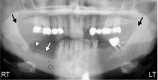

Medication-related osteonecrosis of the jaw (MRONJ) is a rare, severe debilitating condition from unknown causes. It is characterized by nonhealing exposed bone in a patient with a history of antiresorptive or antiangiogenic agents in the absence of radiation exposure to the head and neck region. The first case of MRONJ was reported in the early 2000s. Diagnostic criteria for MRONJ was developed by the American Association of Oral and Maxillofacial Surgeons (AAOMS) based on pharmacological history as well as clinical and radiographic features. Antiresorptive medications such as bisphosphonate and denosumab are currently considered the treatment of choice in patients with osteoclastic bone disease. These reduce bone turnover and improve bone density, thereby improving bone quality. These agents have also been shown to reduce the risk of osteoporotic fractures due to their potent effect in suppressing osteoclastic activity by slowing the remodeling process and increasing bone density, thereby improving quality of life for most of the patients. Despite the great benefits of bisphosphonates and other antiresorptive medications, osteonecrosis of the jaw (ONJ) due to the effects of these medications in the presence of a local risk factor is a significant drawback. Moreover, antiangiogenic drugs play a major role in developing bone necrosis. They are prescribed in cancer cases to prevent metastasis through the blood and lymph nodes. These drugs interfere with the formation of new blood vessels, resulting in ischemia and eventually ONJ. This risk can be managed by evaluating the route and the duration of administration as such a risk can be considered dose-time dependent. As a preventive measure, dental screening before initiating any type of ONJ-related medications can significantly lower the risk of ONJ. Treatment goals can be achieved through pain and infection control, in addition to the management of bone necrosis and resorption. The aim of this review is to identify all causative agents and summarize the preventive measures, diagnostic criteria, and treatment strategies related to MRONJ.

Figures